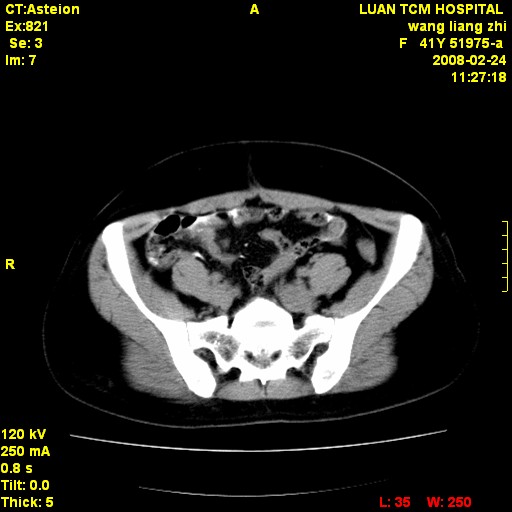

以下是引用dyqct在2009-8-23 16:17:00的发言:[br]考虑:1、造影剂进入腹腔、结肠旁沟、肝周;[br] 2、子宫明显增大(腺肌增生症?);[br] 3、膀胱显影是由于造影剂吸收后经肾分泌进入膀胱的;[br] 4、建议mri检查子宫。